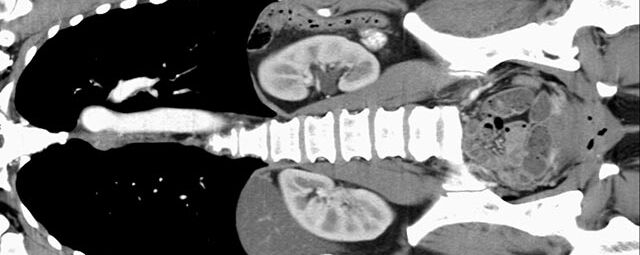

Abdomen (Bauch und Becken)

• Diagnostik von entzündlichen und tumorösen Erkrankungen der Bauchorgane

• Darstellung der großen Gefäße zur Erkennung von Gefäßverschlüssen (z. B. Mesenterial - Arterienembolie oder Einengungen von Gefäßen (z. B. Nierenarterien)

• mehrdimensionale Darstellung vasculärer Strukturen mit zahlreichen Auswertungstools